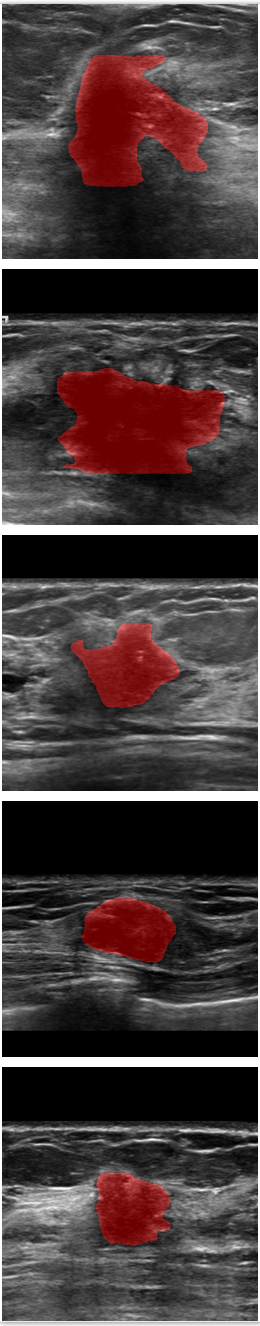

Refer to caption

Figure 7: Comparison of SPCGAN and other segmentation methods of malignant lesions.(a) shows original image of malignant lesions, (b) shows the manual annotation, (c) shows the result of SPCGAN ,(d), (e) and (f) show results from FCN(ResNet), Mask R-CNN and the level set method.

The examples given in Fig.7 correspond to the segmentation results of our SPCGAN, FCN(ResNet), Mask R-CNN and the level set method from malignant lesions. The FCN(ResNet) tends to oversegment the cancer when there is posterior shadowing, especially for the lesion in the first row. SPCGAN shows relatively more robust performance compared to FCN(ResNet), Mask R-CNN and the level set method.